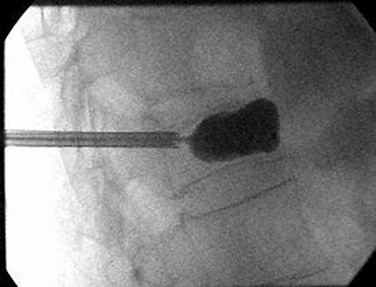

Kyphoplasty is performed under local or general anesthesia. Using image guidance x-rays, two small incisions are made and a probe is placed into the vertebral space where the fracture is located. The bone is drilled and a balloon, called a bone tamp, is inserted on each side. These balloons are then inflated with contrast medium (to be seen using image guidance x-rays) until they expand to the desired height and removed. The spaces created by the balloons are then filled with PMMA, the same orthopedic cement used in vertebroplasty, binding the fracture. The cement hardens quickly, providing strength and stability to the vertebra, restoring height and relieving pain.